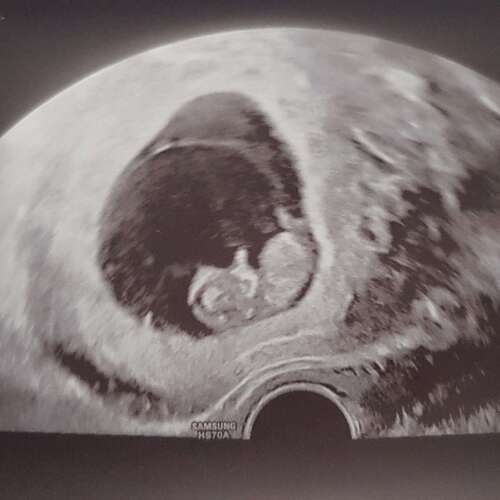

Wir haben heute ein neues bekommen, bei 10+4, sehen unsere erbse aber in 2 Wochen schon zum nipt wieder 🥰🥰 kann es kaum erwarten 🥰🥳